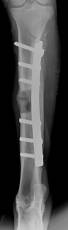

0�� 3���� 12W�� 24W�� 44W